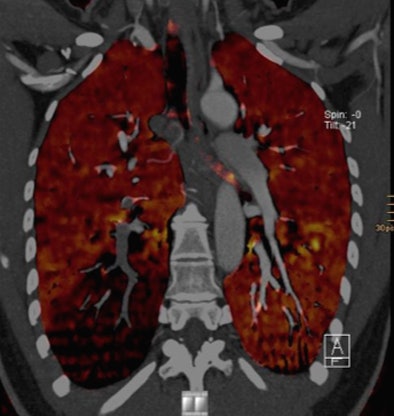

| Above, CTA showing an axial scan with an embolus at the right lower lobe. Below, corresponding coronal pulmonary blood volume map shows a perfusion defect of the right lower lobe. Images courtesy of Tobias de Zordo, MD, and Gudrun Feuchtner, MD. |

On DSCT images, seven patients with pulmonary emboli showed perfusion defects in the corresponding lung parenchyma. In one patient, a triangular perfusion defect was found without a corresponding pulmonary embolus. "We didn't have any additional perfusion defects; we don't know if it's artifact or something else -- the lung window couldn't find anything," he said.